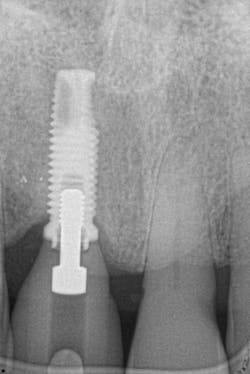

Figure 18: Pre-op radiograph shows retrograde peri-implantitis possibly from previous periapical pathology.

Figures 25 and 26: One-year postsurgery. Clinically all signs of retrograde peri-implantitis have been eliminated and radiographic bone fill can be seen.